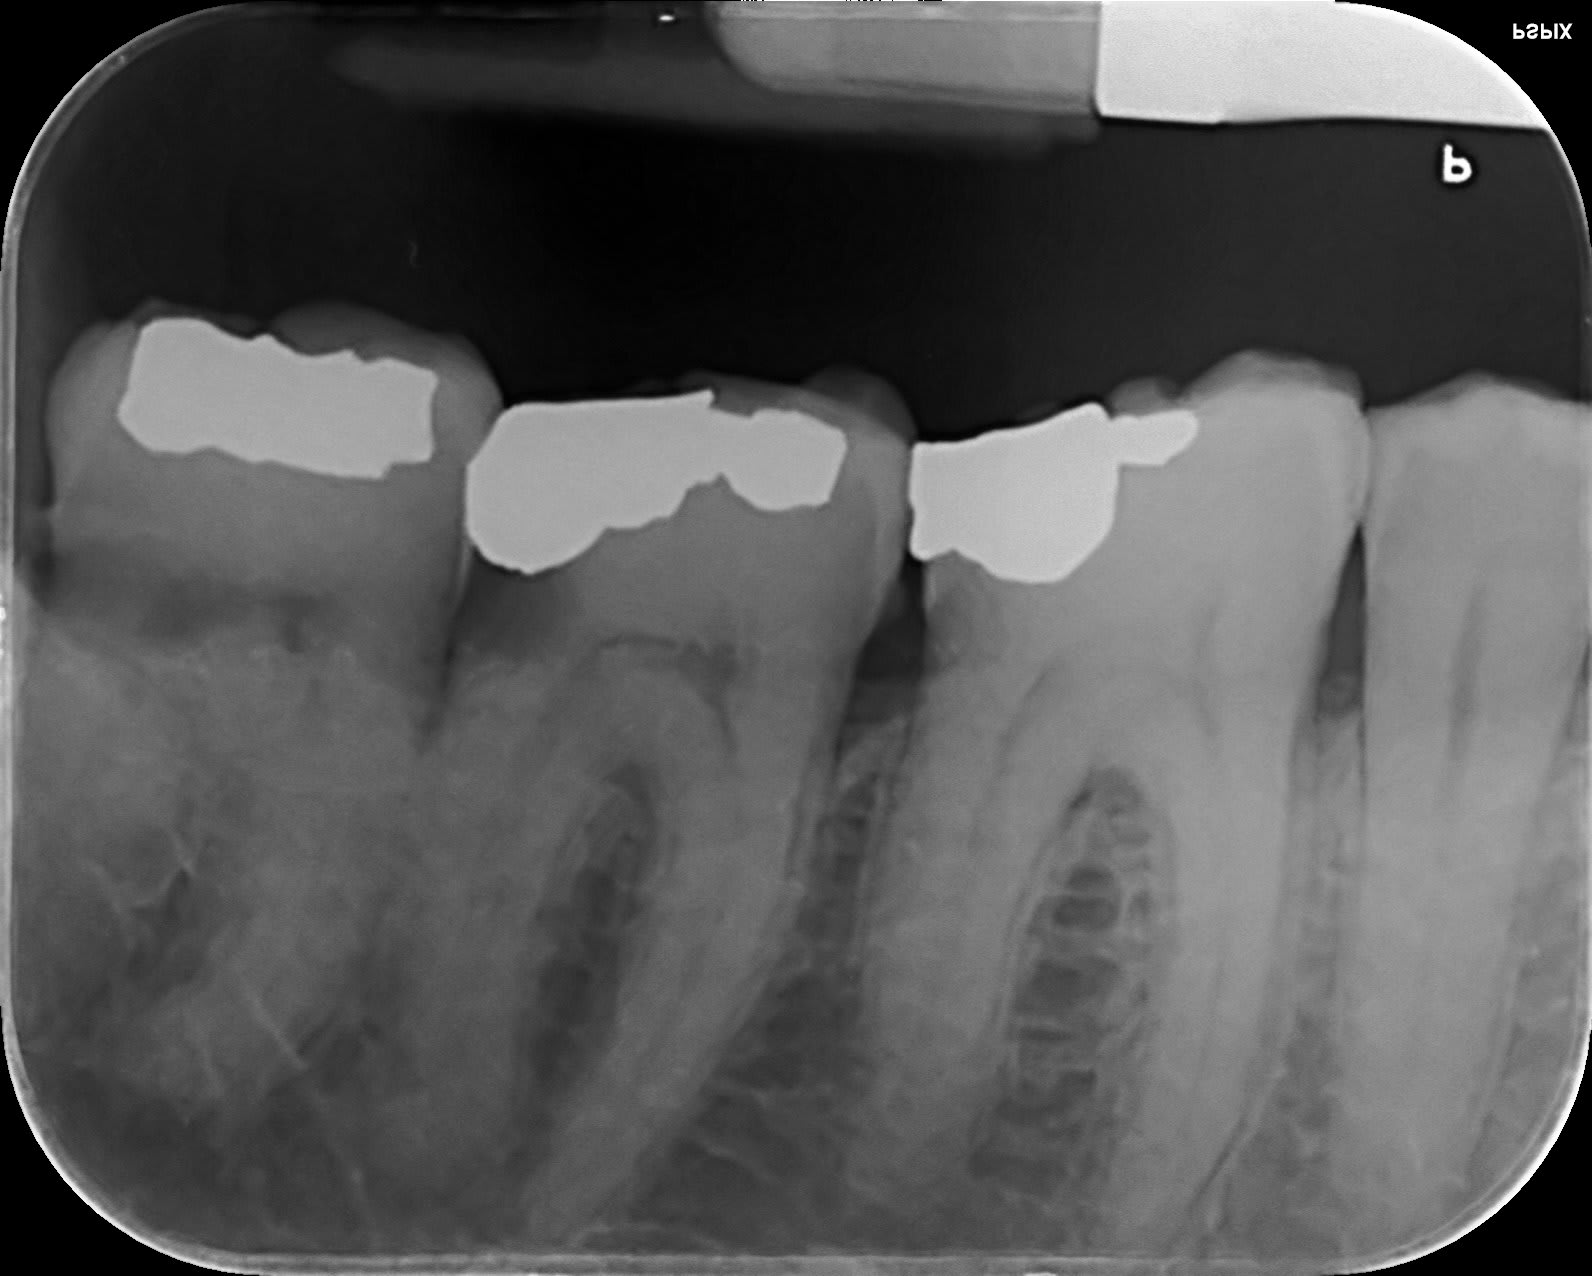

voilà un extrait de fichier de pano..j'ai fait comme j'ai pu pour la conversion de format

Heu, y aurait pas un petit quelque chose aussi sur la racine médiale de 26, comme qui dirait un MV2 oublié. Sinon de l’avis d’enlaye, vu l’évolution pulpaire de cette dent, pourquoi ne pas programmer une endo en sécurité, sous digue . Ca éclaircirai les choses. Bien souvent dans ma pratique une douleur bien localisée sur une dent apparement saine, c’est une fracture liée soit à une chute(parfois anodine) avec l’effet marteau de porte de la mandibule , soit a du clenching nocturne en porte à faux.

CARIDENT.....si j'avais un LIPOE cela se verrait quand même sur la radio..car je n'ai pas l'impression que cela a changé depuis 2016 (voir historique de mes rétro).

Un LIPOE peut passer complétement inaperçu sur une rétro, surtout au niveau des molaires mandibulaires à cause de l’inclinaison des dents. Suivant l'orientation du générateur et du capteur, la superposition des structure sur un cliché 2D peut masquer ce que l'on cherche à voir...